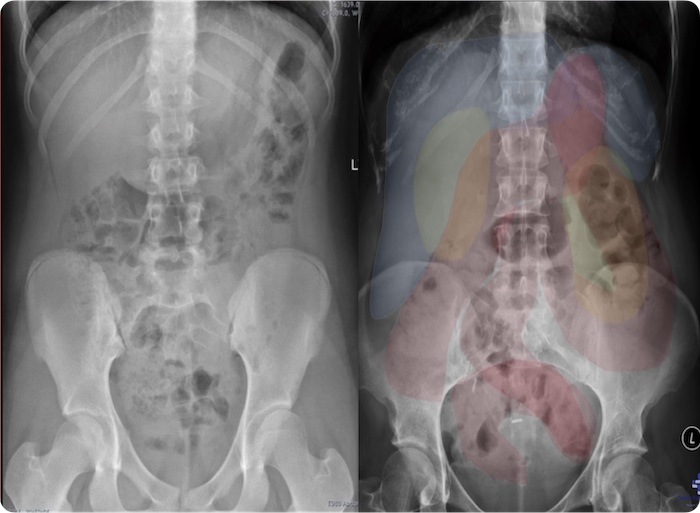

Introduction to Radiology – Chest and Abdomen

- Overview of Radiograph Interpretation

- Systemic Reading Process

- Abnormal Radiographs

- Radiographic Signs of Major Diseases

CT Essentials for the Abdomen and Pelvis

- CT study types

- Identification of bleeding

- Kidney Stones

- Infarctions

- Hernias

- Bowel Obstructions

- Adrenal adenomas